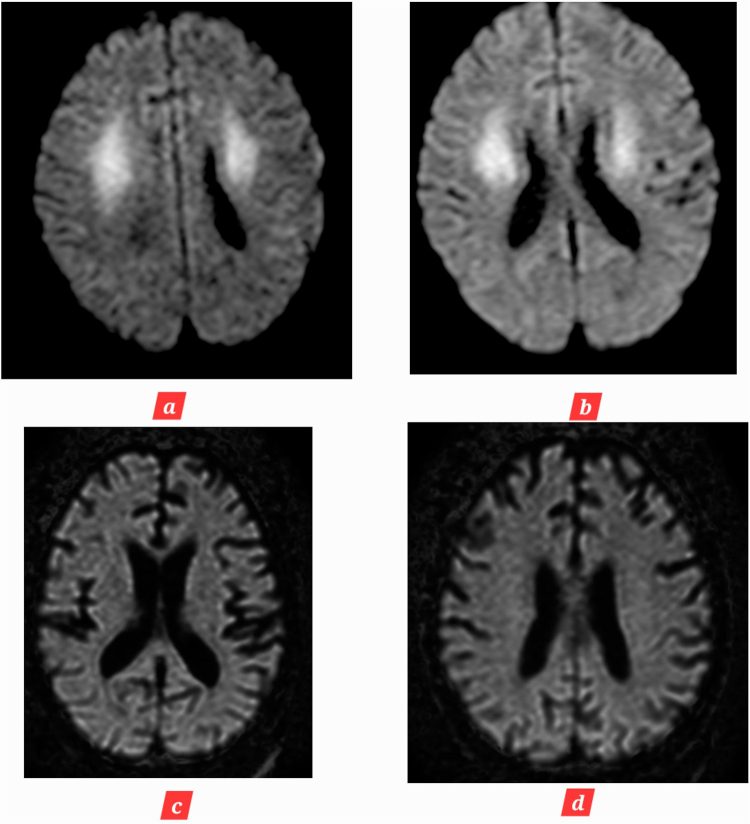

Introduction and importance: Age-inconsistent brain atrophy refers to brain shrinkage that is not proportional to chronological age. This case report is first to report a young patient who developed age-inconsistent brain atrophy due to post cardiac arrest brain injury (PCABI). Due to limitations in the available data, we report our experience and novel magnetic resonance (MR) imaging changes in the brain over the course of 2 months.

Case presentation: We report a case of a 28-year-old woman who developed sudden cardiac arrest during a routine cesarean section, with loss of consciousness for an unspecified period of time. She was resuscitated, intubated and later transferred to intensive care unit (ICU); where her Glasgow Coma Scale on arrival was 4/15. Detailed history, physical examination, and radiological investigations confirmed the diagnosis of PCABI. She was treated in ICU along with physiotherapy for speedy recovery.

Clinical discussion: PCABI is the major cause of long-term disability and mortality following cardiac arrest. In this novel case report, we establish that it can lead to age-inconsistent brain atrophy.

Conclusion: Serial MR imaging scans of the brain should be performed for suspected or confirmed PCABI to evaluate brain atrophy and other changes. This will not only aid in deciphering residual brain deficits but also help in guiding the correct management of the patients.